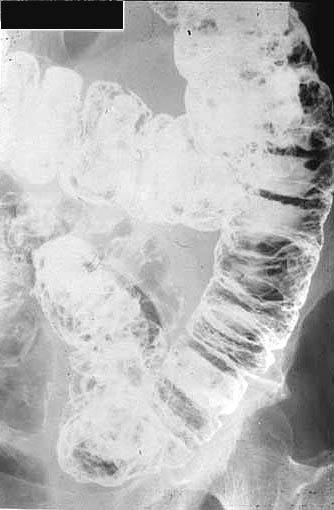

A case of Cronkhite-Canada syndrome with a protein losing gastroenteropathy.

Tokyo Pref., Cooperative study between National Cancer Center and Kyushu Cancer Center (国立がんセンター中央病院, Dr.崎田, 福富)

Tumor-like lesions/Cronkhite-Canada syndorome

Large intestine(Colon)/More than one of the above

X-ray

10 - 14